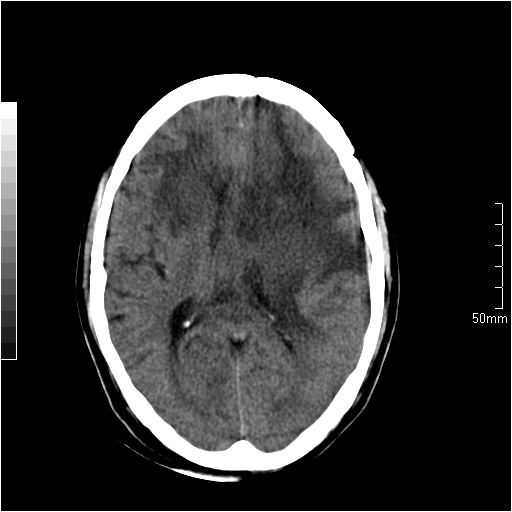

以下是引用天南地北在2007-6-25 12:39:00的发言:[br]有占位效应[br]支持术后复发

以下是引用zjzjr在2007-6-25 12:38:00的发言:[br]左侧复发,右侧转移。